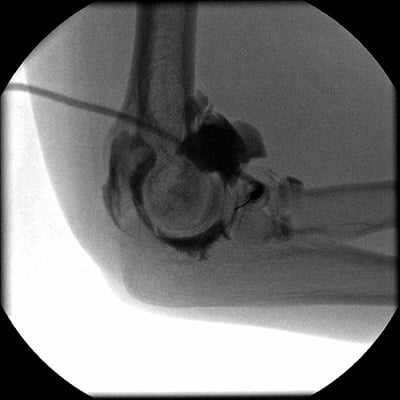

This module will help you achieve optimal images when performing elbow, humerus, shoulder, and scapula examinations. Patient preparation and positioning are discussed, as well as technical settings and patient instructions. Descriptions and images of the expected anatomical structures are included, as well as image evaluation criteria.